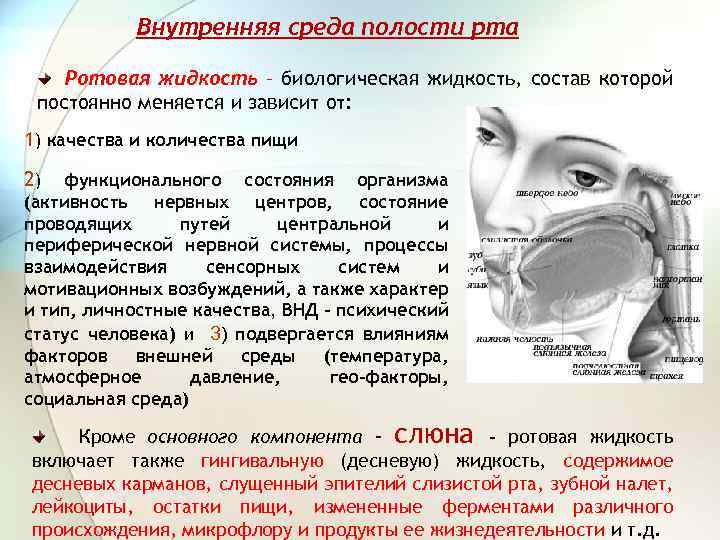

Внутренняя среда полости рта Ротовая жидкость – биологическая жидкость, состав которой постоянно меняется и зависит от: 1) качества и количества пищи 2) функционального состояния организма (активность нервных центров, состояние проводящих путей центральной и периферической нервной системы, процессы взаимодействия сенсорных систем и мотивационных возбуждений, а также характер и тип, личностные качества, ВНД – психический статус человека) и 3) подвергается влияниям факторов внешней среды (температура, атмосферное давление, гео-факторы, социальная среда) Кроме основного компонента – слюна - ротовая жидкость включает также гингивальную (десневую) жидкость, содержимое десневых карманов, слущенный эпителий слизистой рта, зубной налет, лейкоциты, остатки пищи, измененные ферментами различного происхождения, микрофлору и продукты ее жизнедеятельности и т. д.